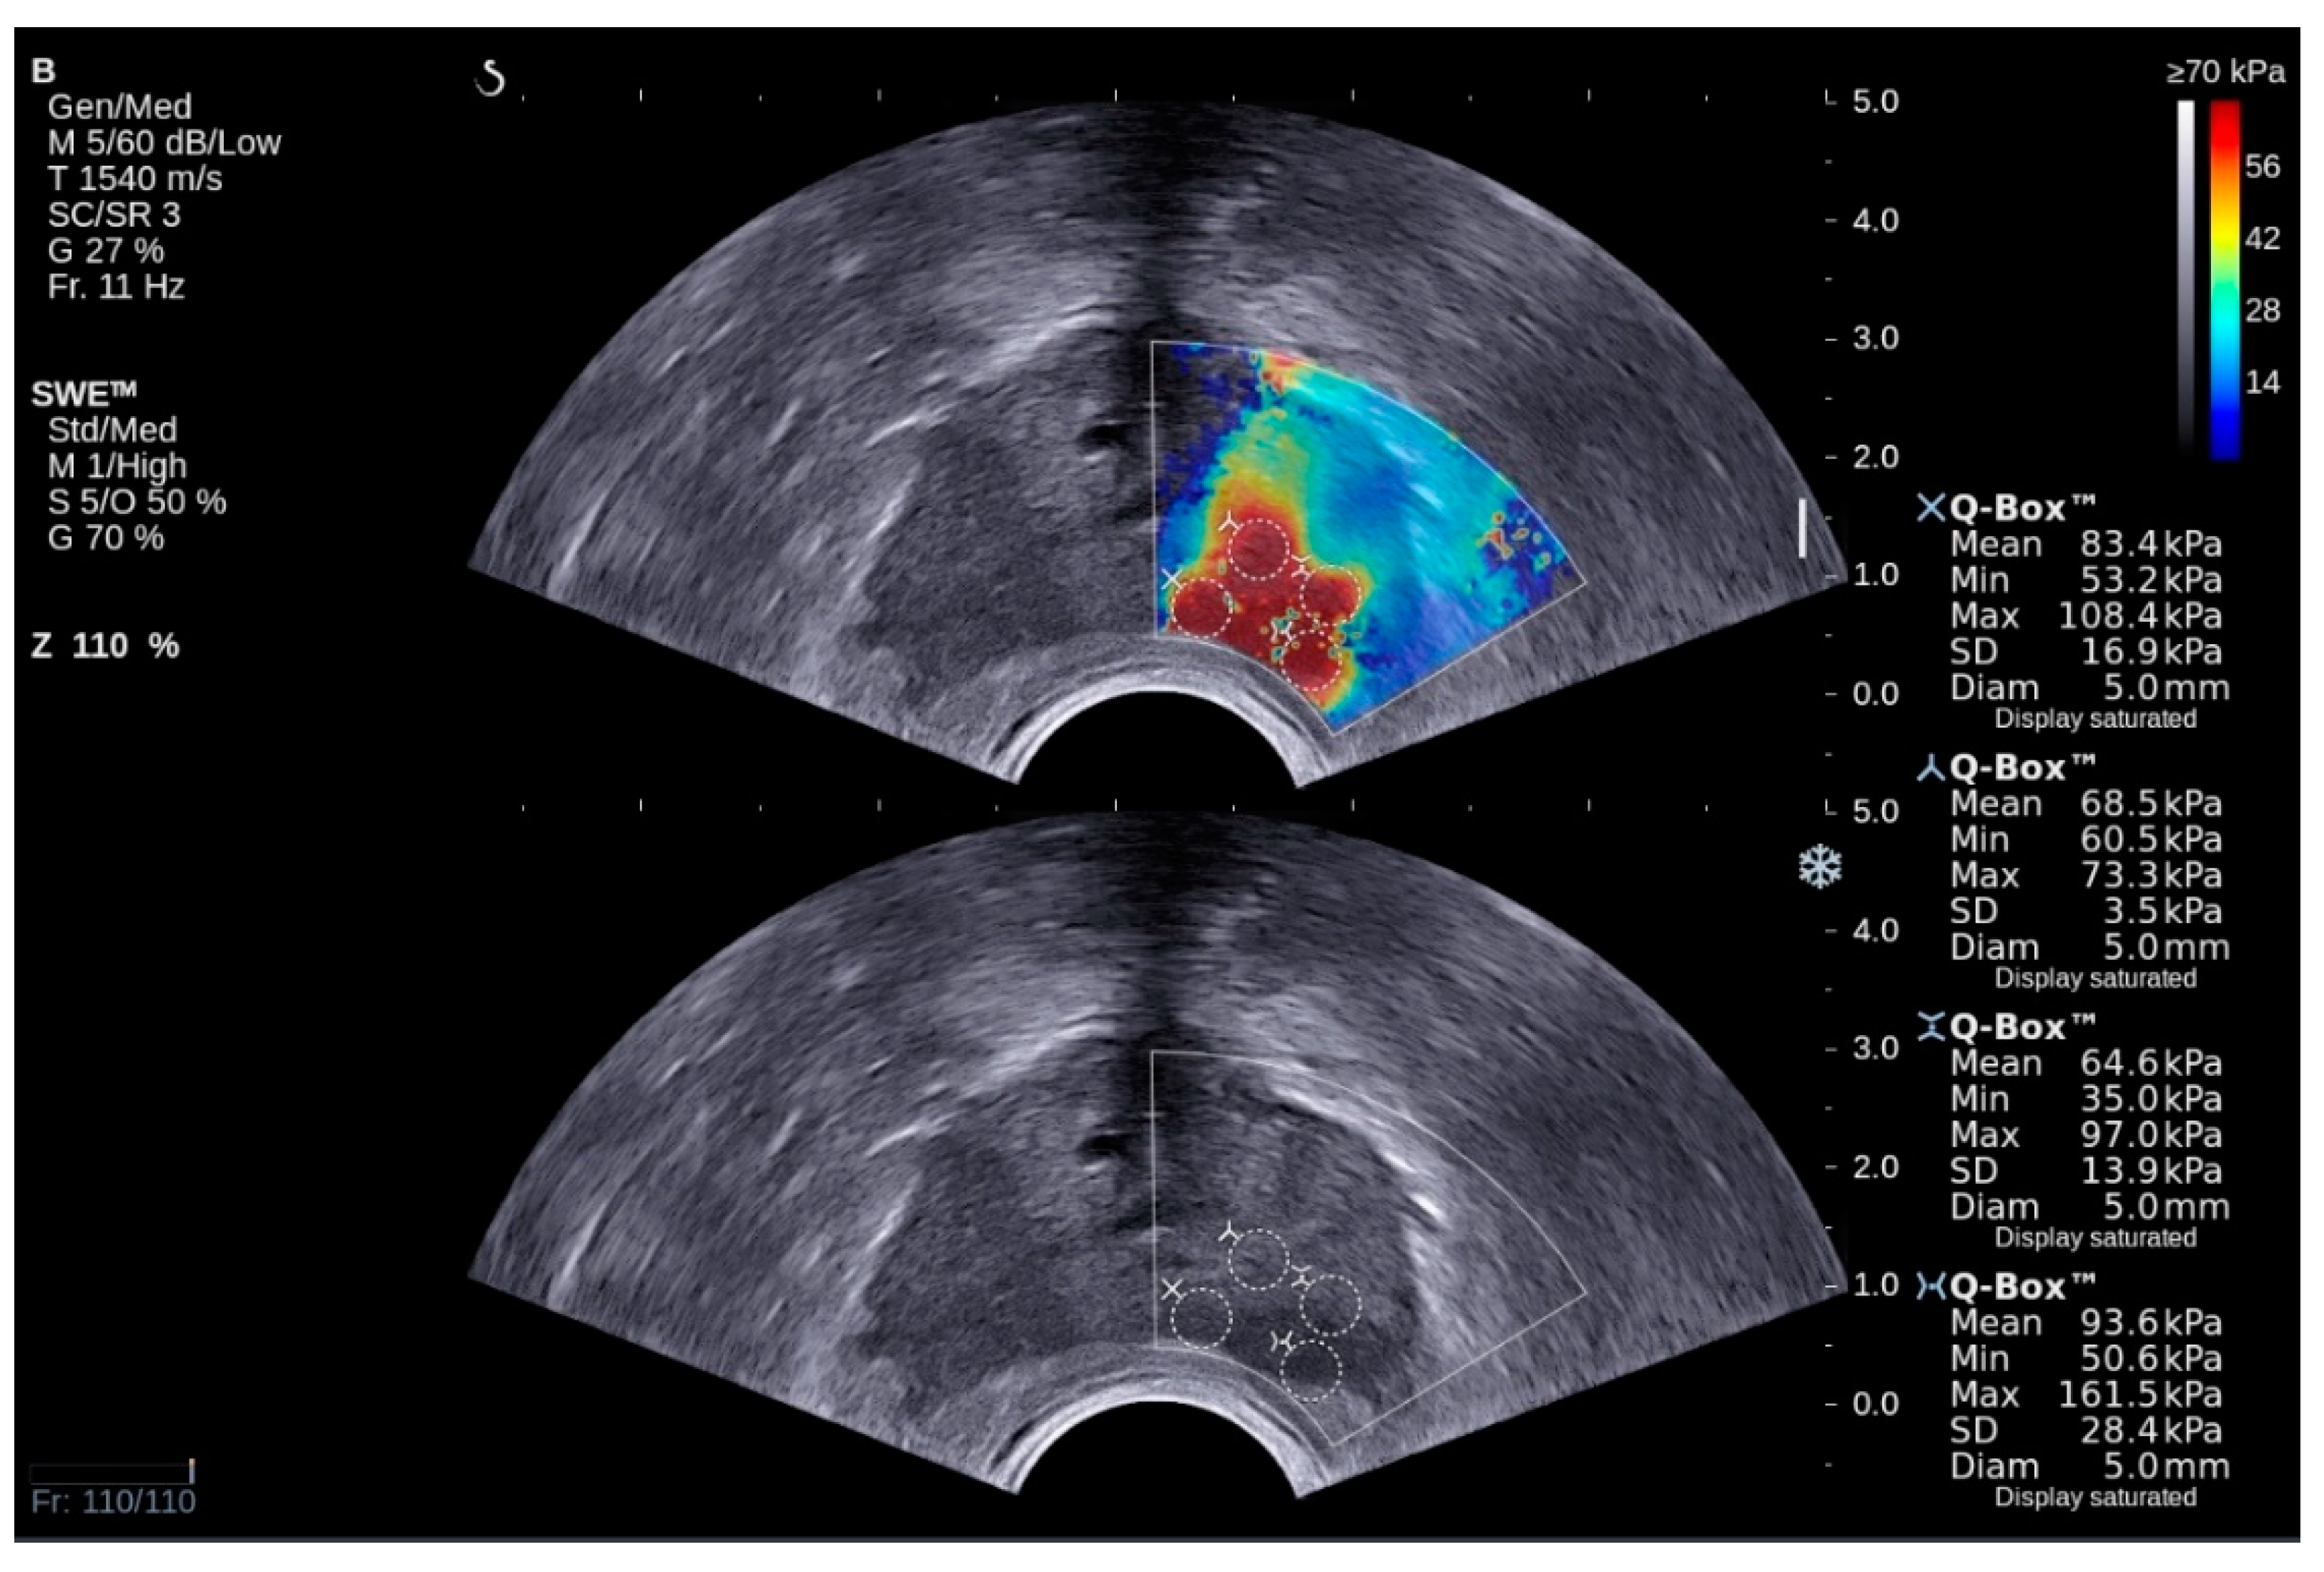

3.1. Methodology for Elastography